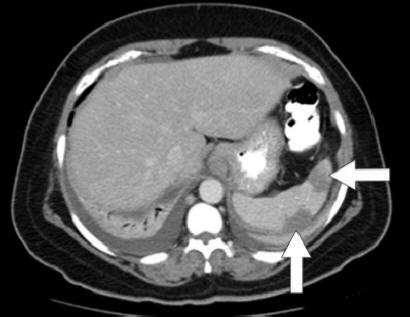

Hepatic infarction. Ischemic hepatitis. ISCHEMIC HEPATITIS (SHOCK LIVER, HYPOXIC HEPATITIS) Hepatic ischemia develops when there is an imbalance between hepatic oxygen supply and demand. Serial CT scans may show resolution of the infarct over weeks, residual scarring, ... Read More

Liver infarcts associated with hepatic artery problems, portal vein narrowing, and hepatic vein obstruction were ruled out by per-forming dynamic liver computed tomography (CT) and Doppler ... Access Content